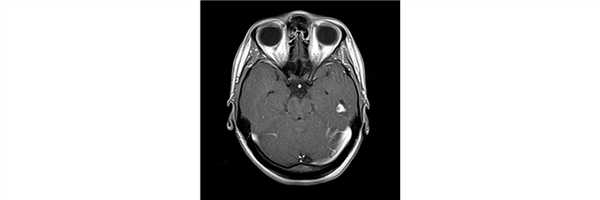

Плеоморфная ксантоастроцитома - редкая доброкачественная (grade II) опухоль центральной нервной системы. Она может локализоваться во всех отделах ЦНС, но наиболее часто обнаруживается в височной доле; при этом инфратенториально (в мозжечке и стволе мозга) она встречается крайне редко - лишь в 8% случаев. В четверти случаев имеет кистозный компонент.

Оптимальным методом диагностики является МРТ головного мозга с контрастным усилением: плохо дифференцируемый узел опухоли в стандартных режимах МРТ (T1WI и T2WI) ввиду его изоинтенсивности мозговой ткани активно накапливает контрастный препарат при введении.

Вследствие активного контрастирования и частого вовлечения оболочек мозга, бескисктозные РХА часто могут быть приняты за менингиомы.

ПКА представляют собой кортикальные опухоли с кистозным компонентом и ярко выраженным накоплением контрастного вещества. Могут иметь место признаки медленного роста, проявляющиеся в отсутствии окружающего отека и фестончатым краем прилегающей кости. Возможно реактивное вовлечение твердой мозговой оболочки, что выражается в виде «дурального хвоста». Кальцификация встречается редко.

ПКА визуализируются в виде солидных узлов, накапливающих контрастное вещество, часто с периферическим эксцентрично расположенным кистозным компонентом (50-60%). Вследствие их периферического расположения и вовлечения лептоменинкса ПКА могут демонстрировать признак «дурального хвоста». Данный признак является следствием реактивности, а не истинного вовлечения твердой мозговой оболочки, что бывает достаточно редко. Поскольку данному типу опухоли характерен медленный рост, имеет место поверхностное ремоделирование прилегающей кости; степень вазогенного отека варьирует.

- Т1: солидный компонент изо- или гипоинтенсивный по отношению к серому веществу; кистозный компонент имеет низкую интенсивность сигнала, лептоменингеальное вовлечение в 70% случаев;

- Т1 с парамагнетиками: выраженное накопление контрастного вещества в солидном компоненте;

- Т2: солидный компонент изо- или гиперинтенсивный по отношению к серому веществу; кистозный компонент имеет высокую интенсивность сигнала; на Т2 FLAIR кистозные компартменты гиперинтенсивны по отношению к ЦСЖ из-за высокого содержания белков; небольшой вазогенный отек;